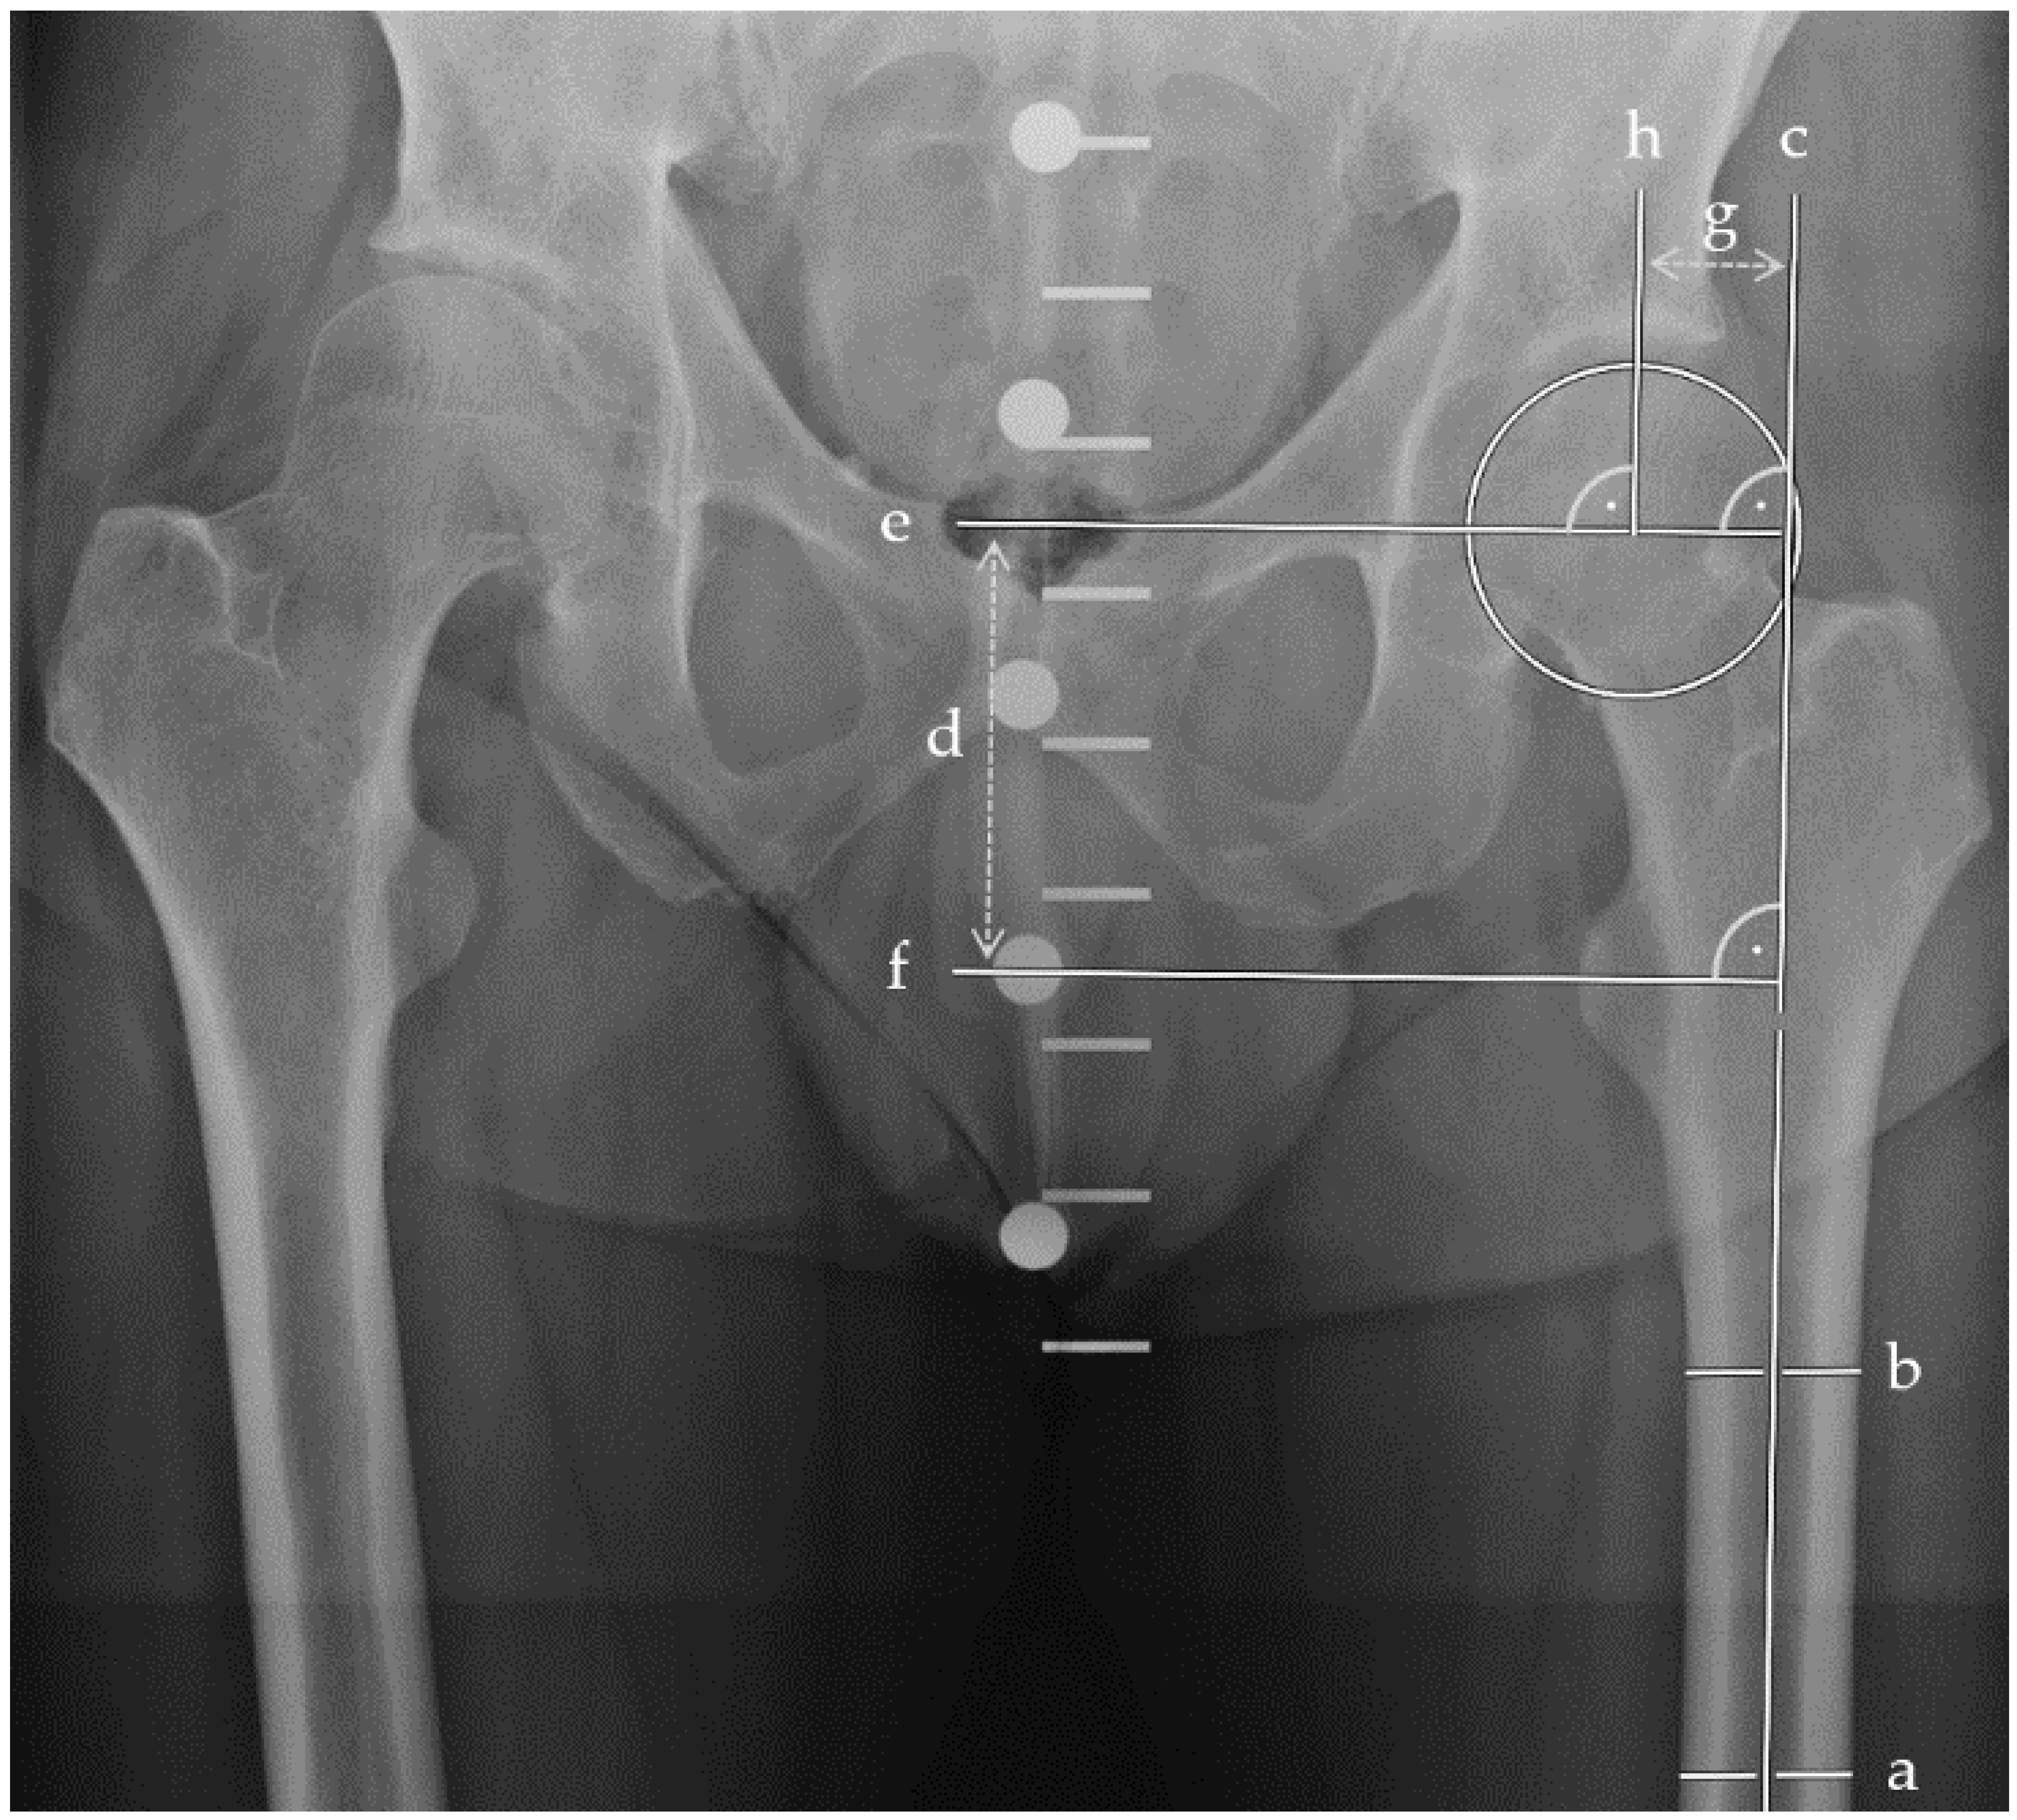

Figure 1.

Plain anterior–posterior radiographs of the pelvis visualizing leg length and femoral offset measurements. Two parallel bisections of the femoral shaft (a, b) determined the longitudinal femoral shaft axis (c). Perpendicular to (c), the leg length (d) was measured between the femoral head centre (e) and the tip of the lesser trochanter (f). The femoral offset (g) was measured between the femoral head center (h) perpendicular to (c).